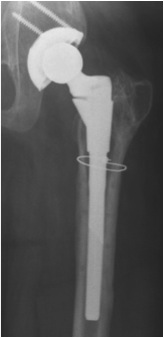

Technique

Surgical technique PDF Hip Conversion Robotic Assistance

Surgical technique PDF Hip Conversion image less navigation

Youtube surgical technique Hip Conversion image less navigation

- consider image less navigation / CT guidance / robotic guidance